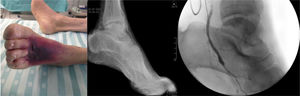

Como en cualquier otra afección, el primer paso para el diagnóstico es el examen físico, valorando el riesgo quirúrgico del paciente y la herida. La herida, clasificada con base en los criterios WIfI8, determina la urgencia del procedimiento, el tipo revascularización más indicada, la arteria diana, el tipo de conducto y el pronóstico del miembro y del paciente (fig. 1).

En seguida, todos los pacientes son sometidos a eco-Doppler arterial y venoso. Este examen es clave en la evaluación inicial del paciente, proporcionando información sobre el tipo de enfermedad, el influjo del bypass y las arterias diana. El mapeo venoso nos permite identificar venas autógenas de diámetro adecuado. Un diámetro mínimo de 3mm es ideal para la mayoría de las revascularizaciones, pero aceptamos venas entre 2,5 y 3mm para bypass a arterias inframaleolares. Preferimos un segmento único de safena interna, pero consideramos venas alternativas y, en último caso, anastomosar 2 segmentos venosos de buen diámetro.